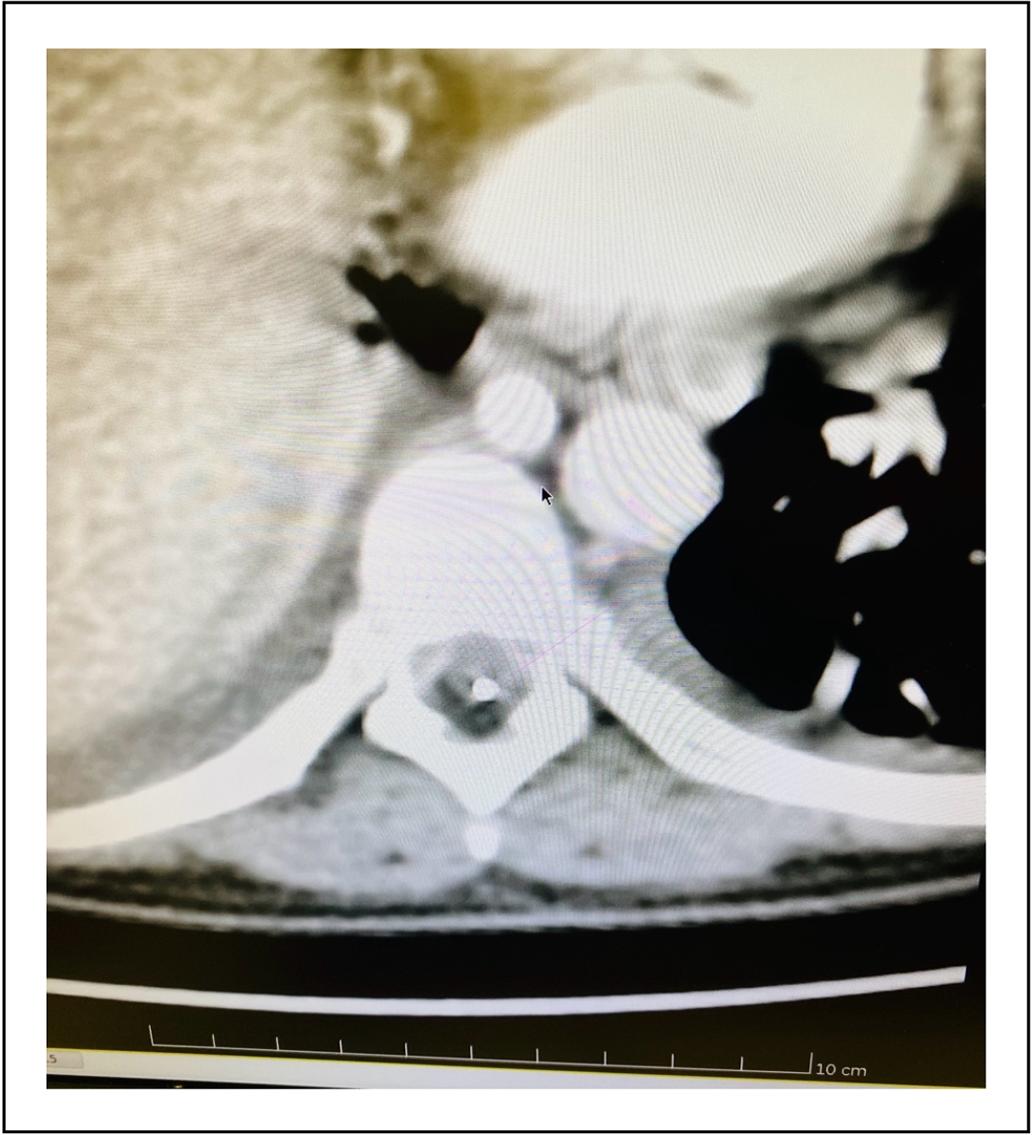

Se comenzó con una infusión de 600 /μg día de Morfina IT con optimización franca de la analgesia y sin efectos adversos. Los rescates analgésicos se establecieron vía oral con Licor de Brompton (LB). Se realizan ajustes en domicilio según la evaluación del reporte de la paciente, aumentándose un 20-30% de dosis basal, cuando lo requirió, hasta obtenerse alivio. Al mes post colocación de bomba IT, se produce nueva escalada de dosis. Se realiza TAC con reconstrucción tridimensional del trayecto del catéter para confirmación de la posición de punta de catéter, comprobándose su correcta colocación. (Figura 2).

Figura 2. Tomografía Axial Computarizada que muestra posición del catéter intratecal en topografía posterior al canal medular.

Al mes de colocación, la paciente refiere dolor transfixiante torácico severo y persistente en el área torácica, lo que motiva una rápida escalada de dosis de opioides. Esta situación se puede interpretar como un indicador de tolerancia opioide. Ante la duda y la posibilidad de progresión de la enfermedad o bien malposición de la punta del catéter, se realizó una TAC del trayecto del catéter con reconstrucción 3D, que confirma la colocación adecuada del mismo así como documenta severa progresión lesional.